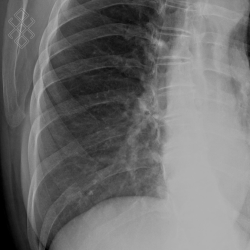

Radiographie du Gril costal